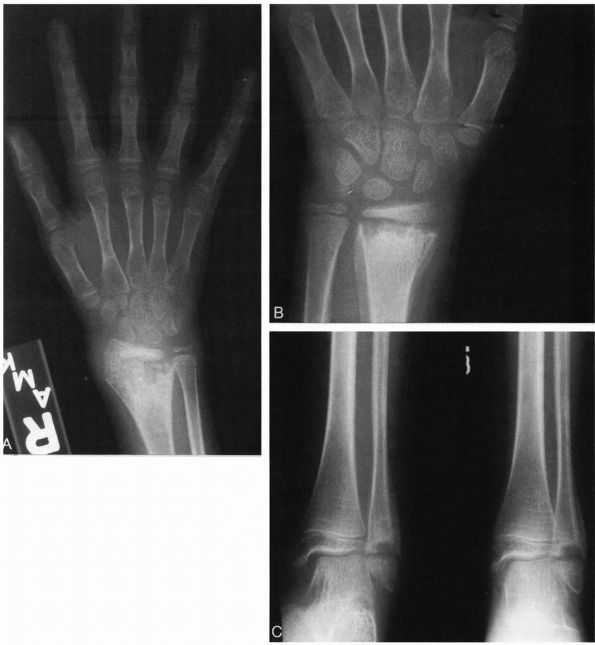

![]() |

Radiographs of an 8-year-old girl with chronic multifocal osteomyelitis who had a longer than 2-year history of multiple sites of bone pain. (A) AP radiograph of the right wrist demonstrating bone destruction of the metaphysis, physis, and epiphysis. (B) AP radiograph of the left wrist demonstrating bone destruction in the metaphysis with periosteal reactive bone. (C) Radiographs of the left ankle demonstrating metaphyseal and physeal destruction of the distal fibula with periosteal reactive bone. |